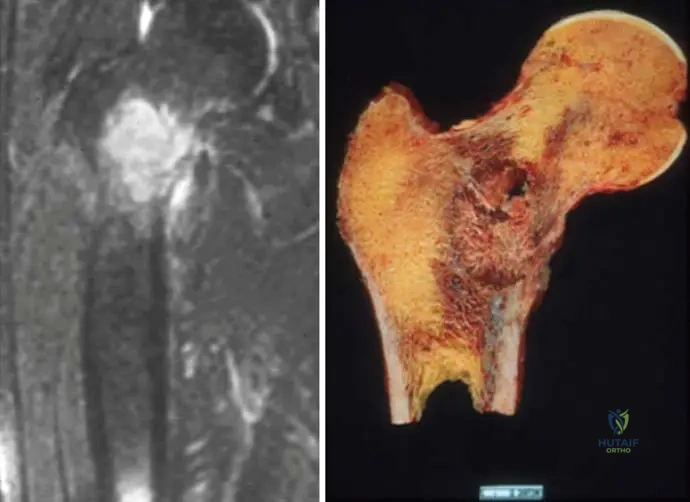

A 57-year-old male presents with a 2-month history of progressive left arm pain and weakness. Radiographs reveal a lytic destruction of the shaft of the left humerus. A subsequent bone scan shows increased uptake in the affected area, and a CT abdomen identifies a primary site in the kidney. What is the expected radiographic appearance of metastatic bone disease?

View Answer & Explanation

Correct Answer: D

Rationale: The clinical text explicitly states, "The radiographic appearance of metastases is highly variable. The appearance will vary from radiolucent to radiodense; some tumors have a mixed character." This directly addresses the variability in radiographic presentation. The image (Fig. 8.123a) shows a lytic lesion, but the text emphasizes the broad spectrum. Options A, B, and C are incorrect because they suggest a single, consistent appearance.

Question 89

A 57-year-old male presents with a lytic destruction of the shaft of the left humerus. A bone scan shows increased uptake in the lesion, and a CT abdomen reveals the primary site in the kidney. What is a characteristic feature of metastatic lesions originating from kidney cancer?

Correct Answer: B

Rationale: The image (Fig. 8.123a) shows a lytic destruction of the humerus, and the caption states the primary site is the kidney. Kidney cancer (renal cell carcinoma) metastases are classically known for being purely lytic and highly vascular, often presenting with significant bone destruction and sometimes hemorrhage. Blastic lesions (A) are more typical of prostate cancer. The text mentions kidney cancer as a frequent primary for bony metastases, and the image provides a specific example of a lytic lesion from a kidney primary.